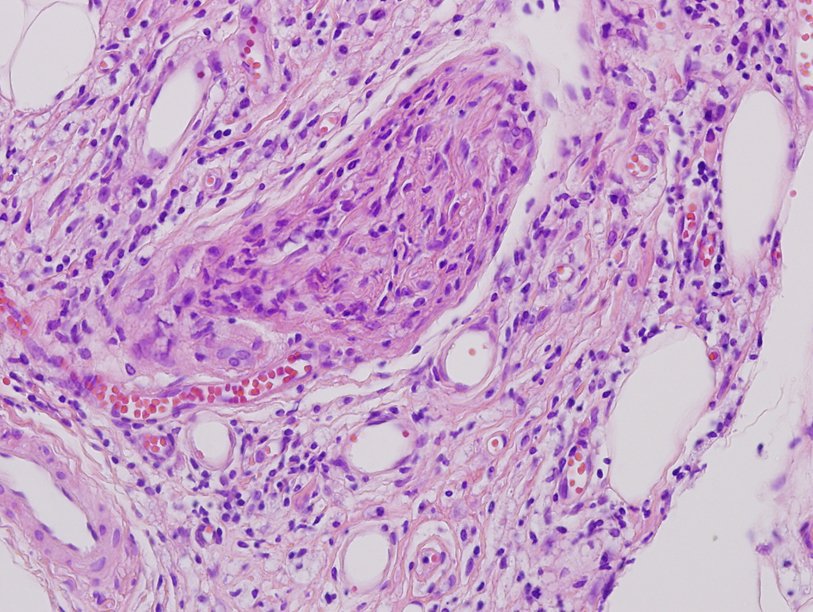

Desmoid-Type Fibromatosis

#OnePathboardPointAtATime • Locally-aggressive clonal myofibroblasts • Long, sweeping fascicles • Infiltrative growth • Collagenous stroma • Bland spindle cells • Low N:C ratio • Elongated ovoid nuclei • May have hyalinized or edematous areas pic.twitter.com/3bRBiakb66